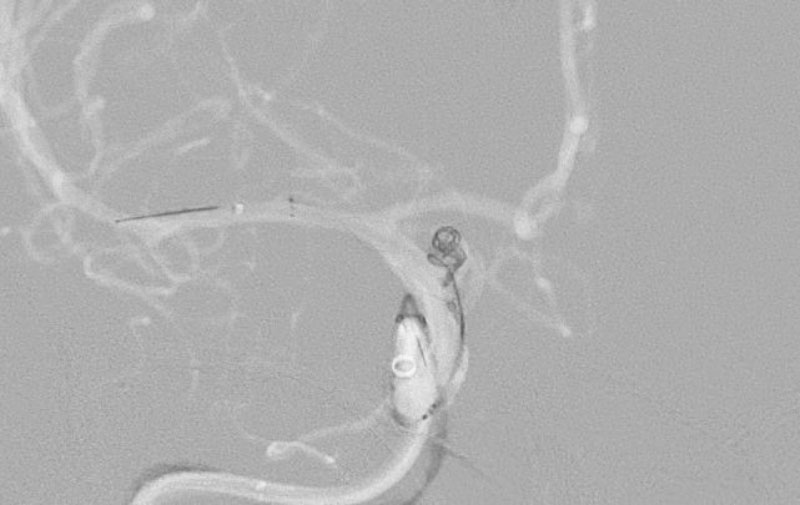

'25年11月

くも膜下出血

破裂性内頚動脈解離

40代

救急外来

No.1594 手術中